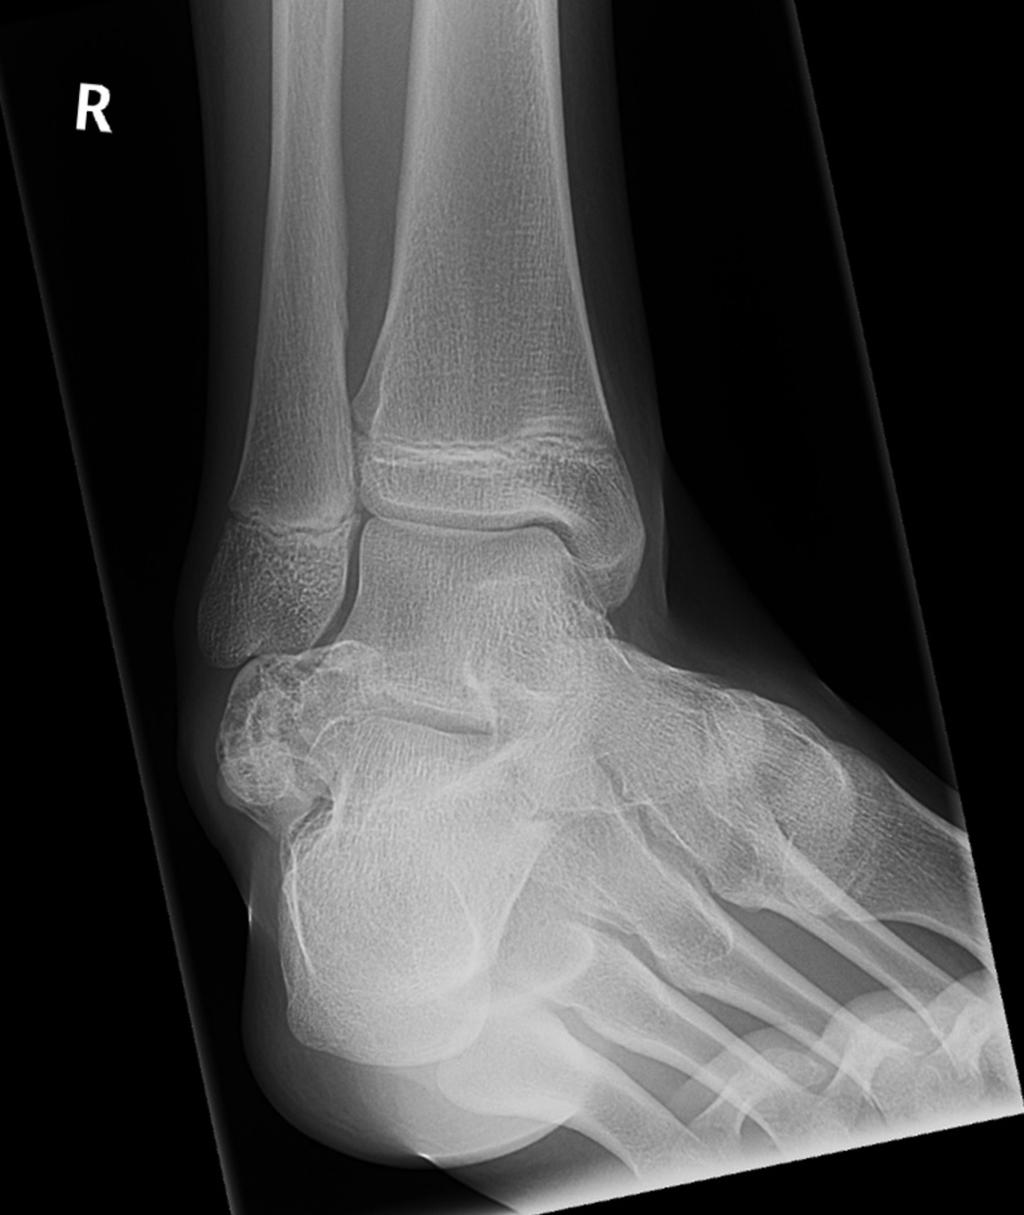

Gepubliceerd: Week 45 - 2019 211 deelnemers Een 15-jarige jongen komt op de polikliniek Orthopedie vanwege een pijnloze, langzaam groeiende zwelling van de dorsolaterale zijde van zijn rechter enkel. Wat is de diagnose? Wat is uw diagnose? Antwoord ziekte van Trevor os trigonum geossificeerde synoviale chondromatose chondrosarcoom Antwoord controleren